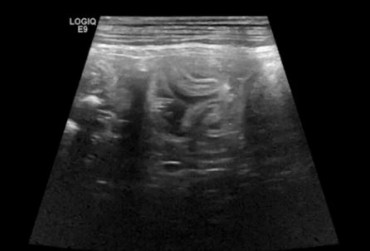

Zarażenie psa pasożytem nicieniem Dirofilaria immitis – opis przypadku

W artykule opisano przypadek dirofilariozy u psa wywołanej D. immitis. U badanego pacjenta stwierdzono patognomiczny obraz zmian w badaniu rentgenowskim i ultrasonograficznym układu sercowo-naczyniowego.